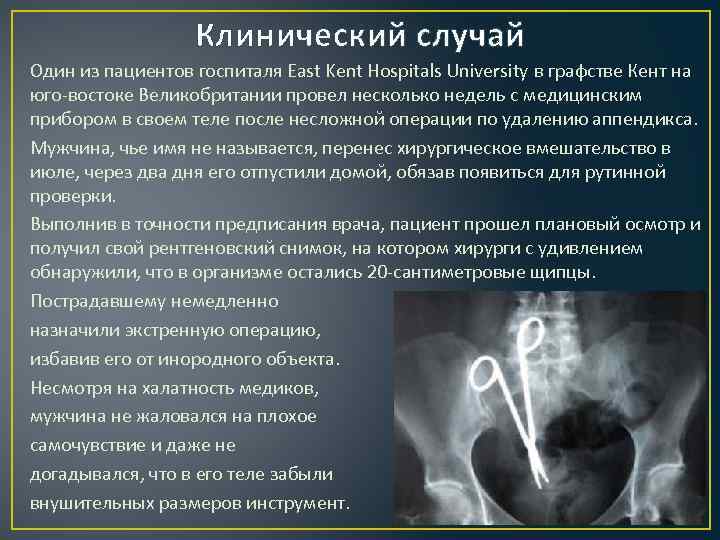

Необычные находки: инородные тела на рентгенограмме брюшной полости

Раздел: Мудрость в деталях